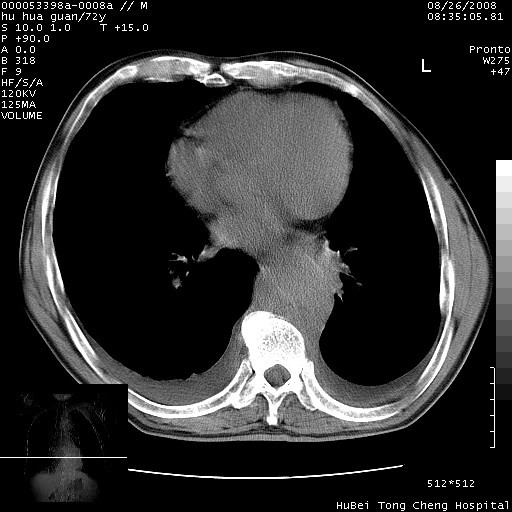

考虑胸主动脉下段夹层破裂。

考慮夾層動脈瘤破裂可能,建議增強掃描。

可以明确的说。肯定不是主动脉夹层破裂出血!考虑为淋巴瘤或间叶组织来源的恶性肿瘤可能性大。右肺小结节建议薄层观察,如能发现恶性征象,那椎前改变就考虑为转移所致。至于双侧少量胸水乃静脉血回流受阻所致。

图像及窗宽窗位均不理想。周围性肺癌/胸腔积液/纵隔积液。

降主动脉前移位,后纵隔占位

后纵隔占位,降主动脉前移位;双侧胸腔积液;应排外食管病变侵犯血管可能;

主动脉瘤破裂